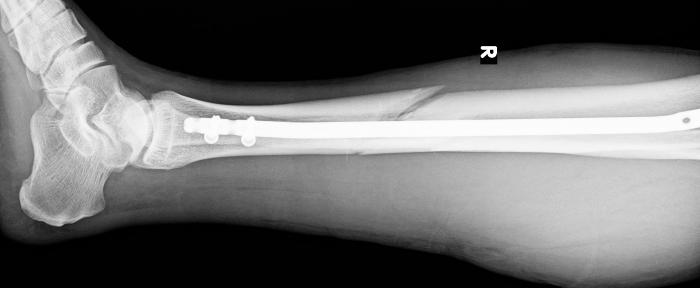

Операция прошла под песни, затем капельницы в обе руки и кислород в нос. На следующий день фото: чего они там насвинчивали (18 шт. саморезов).

И вот в таком, как детеныш терминатора, виде (в буквальном смысле титановая нога), сейчас я начал планировать поездку на горнолыжный курорт в 2016 году. Поначалу я хотел удалить эти две титановые пластины из ноги и даже списывался и получил утвердительный ответ от того австрийского хирурга. Но потом так сложилось, что эти снимки я показал главному военному ортопедическому доктору в одной из израильских клиник. И он на чистом иврите, с заимствованиями из русского, мне сказал «а нафига», в оригинале прозвучало сильней. Типа не болит, не мешает. Я его заверил, что прыгать с парашютом не планирую, но кататься на лыжах с гор хочу и буду. И тут он тоже продемонстрировал свое знание английского, сказав okay, you can ski.